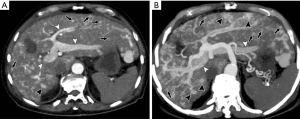

This is a direct demonstration of a HAPS, usually due to a high-flow arterial fistula, generally a macroscopic arterioportal fistula, transvasal or transtumoral shunt. Two practical findings make this observation easier to diagnose: (I) early main portal vein enhancement, occurring before either the splenic (SV) or superior mesenteric vein (SMV); or (II) early enhancement of peripheral portal vein branches before the common portal vein (Figure 2). Frequently early enhancement will also demonstrate early venous opacification, which can be temporally close to the timing and intensity of the abdominal aorta in the setting of a large shunt.

THED

THED indicate transient increased attenuation or signal intensity differences during the HAP, which return to normal or near-normal in the portal venous phase (PVP) and equilibrium phase. It typically manifests as a peripheral, wedge or cone shaped area with a straight margin, and contains normal vessels (Figure 3). THED usually occur in functional HAPS (transsinusoidal shunts and transplexal shunts) caused by decreased portal or hepatic venous flow due to contrast material passage from the high-pressure arterial blood into a low-pressure portal vein branch, thus enhancing a focal area of the liver before the adjacent parenchyma is enhanced through flow from the normal portal venous system (18,19).